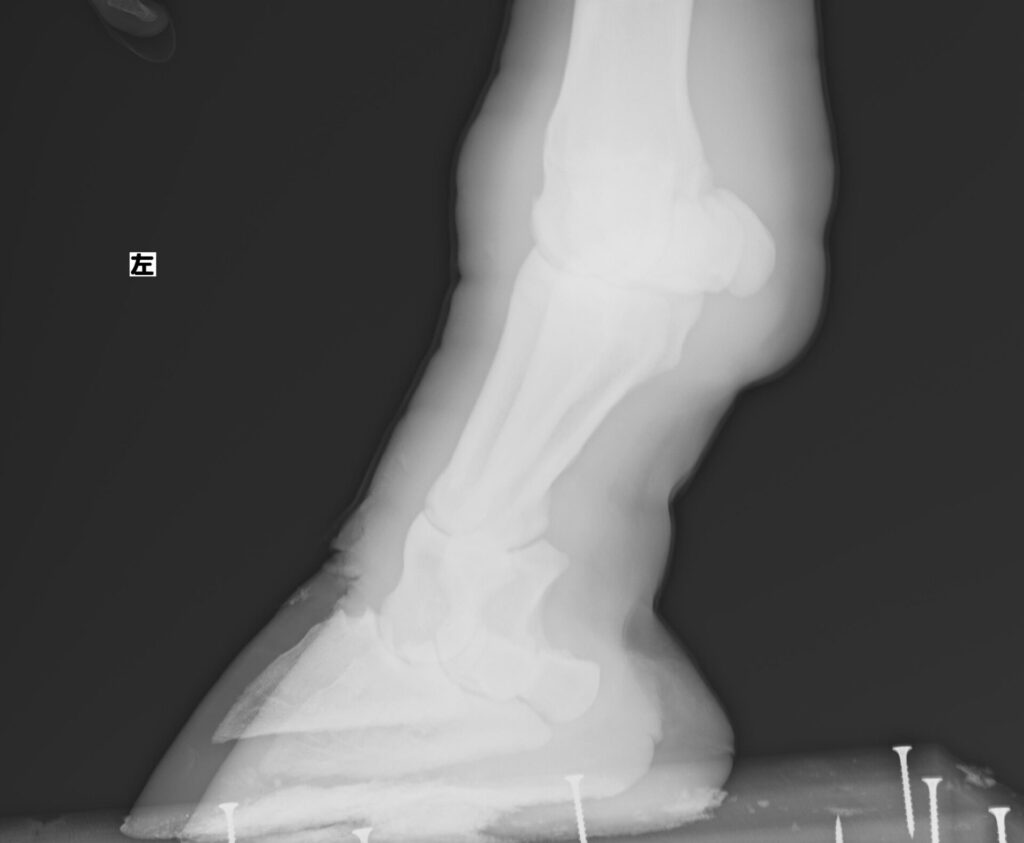

また外見だけではわからないこともあるため、肢のレントゲン撮影にも取り組み始めました。撮影の間じっとしていてもらわなければならないので練習して本番に挑んだところ

撮れました!!

獣医さんいわく今のところ異常なしとのことでホッとしました。

定期的に撮影して骨に異常がないか確認していきたいと考えています。